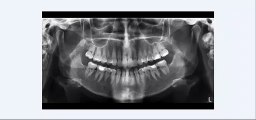

man unterscheidet offene oder geschlossene knochendehnung. zum geschlossenem bone spreading findet ihr hier ein video https://dai.ly/x7tcm84 generell findet ihr fortbildungsvideos in unserer playlist https://www.dailymotion.com/playlist/x6642 sollte ein video / thema nicht dabei sein, dann bitte einfach schreiben und ich werde es ehemöglichst abarbeiten. geschlossenes bonespreading ist immer der offenen variante vor zu ziehen, denn die blutversorgung des knochens bleibt erhalten. nur bei extremen spitzkamm wie in diesem fall ist eine offene vor zu ziehen.